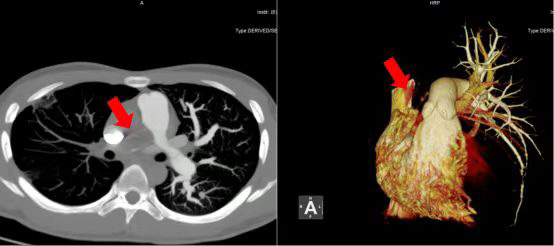

CT检查发现,王某的整个右肺动脉主干已经严重堵塞,随时有缺氧发作、晕厥、甚至猝死的风险。相比表姐,他的病情更为严重。万幸的是,他的病情被及时发现并确诊,能够在疾病早期进行手术干预,尽最大可能保留心肺功能。如果发现得越晚,手术风险越高,甚而失去手术机会,如果放任病情不管,随着肺动脉高压的上升和心功能的下降,一旦发生心力衰竭,患者的预期寿命将不超过五年。

王某术前肺动脉CTA(箭头示被血栓闭塞的右肺动脉)

在心脏大血管外科、重症医学科、呼吸内科、心脏内科、麻醉及体外循环等多科室的周密准备和密切配合下,表姐弟两人按计划先后进行了肺动脉内膜剥脱手术治疗,术后恢复良好,肺动脉基本恢复通畅,肺高压较术前明显下降,平稳出院。

王某术后肺动脉CTA(右肺动脉已恢复通畅)